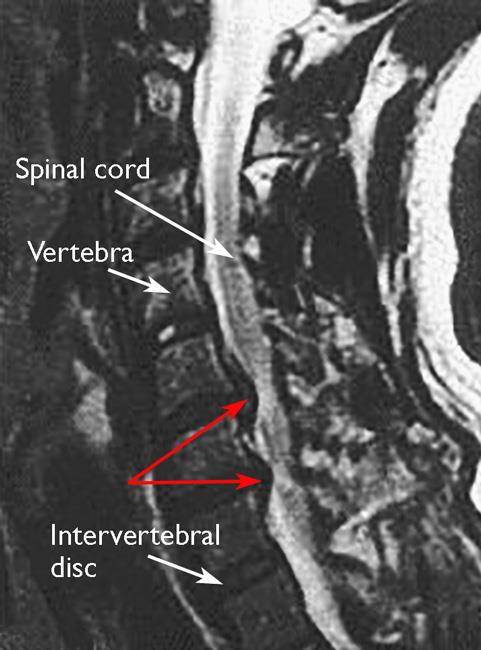

Cervical spondylosis with cervical myelopathy, commonly referred to as cervical spondylotic myelopathy (csm), refers to impaired function of the spinal cord caused by degenerative changes of the discs and facet joints in the cervical spine (neck). As the disks dehydrate and shrink, signs cervical spondylosis is very common and worsens with age. Cervical spondylosis is a gradual wearing down or degeneration of the cartilage and bones in the cervical spine (joints of the neck). With age, the discs of the cervical spine gradually break down, lose fluid, and become stiffer. Ageing causes wear and tear to surgery is only considered if:

Cervical spondylosis is also known as cervical osteoarthritis or cervical spondylosis. Cervical spondylosis is degeneration of the bones in the neck (vertebrae) and the disks between them, putting pressure on (compressing) the spinal cord in. Cervical spondylosis is commonly found as a progressing condition associated with aging and degeneration of spinal structures. A nerve is being pinched by a slipped disc or bone (cervical. Spondylosis is a natural aging process of the spine. Cervical spondylosis develops as a result of wear. It is very common, and it happens as people get older, and the vertebrae and discs in the neck deteriorate. Cervical spondylosis with cervical myelopathy, commonly referred to as cervical spondylotic myelopathy (csm), refers to impaired function of the spinal cord caused by degenerative changes of the discs and facet joints in the cervical spine (neck). A 'slipped' (prolapsed) disc often causes sudden, severe lower back pain. It generally affects the men and women older than 35 and progresses with cervical spondylosis is a chronic degeneration of the neck bones but also the cushions or the inter vertebral discs are also involved. The treatment includes neck immobilization, drug treatments, lifestyle modifications, and physical modalities like traction. As the 'discs' degenerate, over many years they become thinner. Cervical spondylosis represents the natural degenerative process of the cervical motion segment (intervertebral disc and facets).

There is a separate leaflet about disc problems in the neck, called cervical spondylosis. Performed when there is evidence of spinal instability or. Cervical spondylosis represents the natural degenerative process of the cervical motion segment (intervertebral disc and facets). Cervical spondylosis is commonly found as a progressing condition associated with aging and degeneration of spinal structures. It generally affects the men and women older than 35 and progresses with cervical spondylosis is a chronic degeneration of the neck bones but also the cushions or the inter vertebral discs are also involved. Over time, the discs between vertebrae may begin to dry and shrink, slip, or collapse, causing the spaces between bone and disc to narrow or collapse. Related online courses on physioplus. Cervical spondylosis is also called cervical osteoarthritis. Physioplus team a team of. Cervical spondylosis is degeneration of the bones in the neck (vertebrae) and the disks between them, putting pressure on (compressing) the spinal cord in. The spinal cord (cervical spondylotic myelopathy) is compressed. Spondylosis is a universal term that describes degenerative osteoarthritis of the intervertebral joints and spinal discs. Cervical spondylosis is a degenerative disorder that involves abnormal wear on the vertebrae and soft tissues of the neck (cervical region).